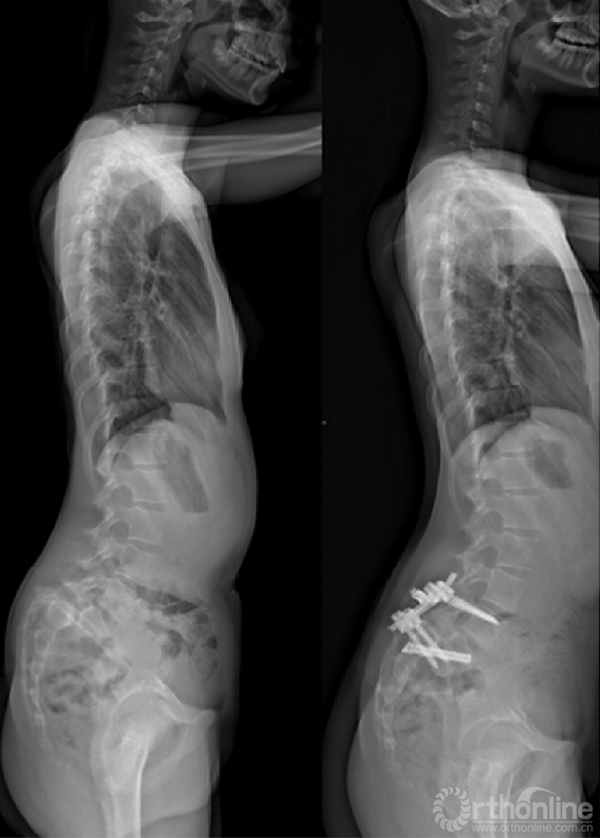

② 明显失平衡者,采取后路复位联合前路支撑重建术式。

① 采取前后联合,骶骨部分截骨、复位和椎间支撑重建手术[8]。

② 我们的病例